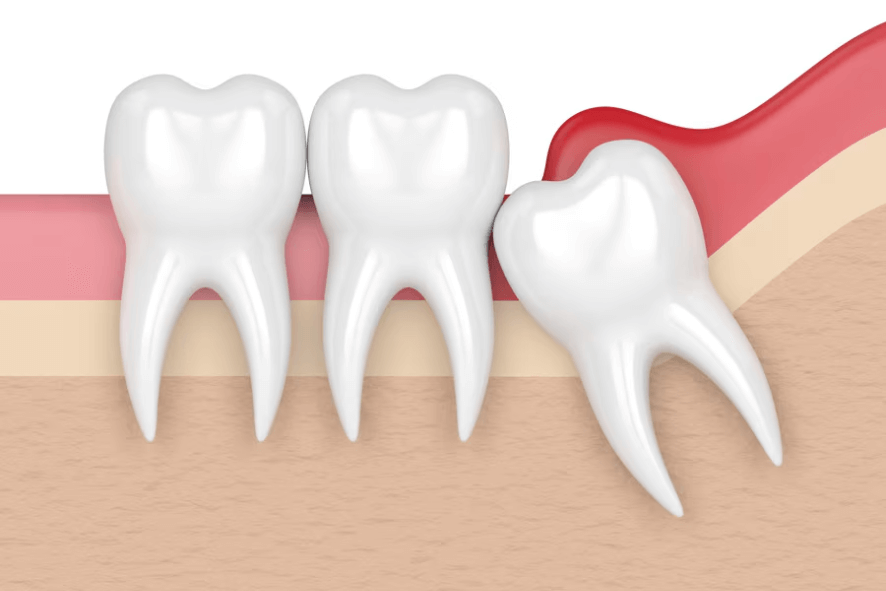

🔹 Dor ou inchaço na gengiva

🔹 Cistos ou reabsorção óssea

Além da dor, o que muitos não sabem é que o preço de não extrair o siso pode ser alto:

Um siso mal posicionado pode causar problemas no dente vizinho como: cárie, perda óssea, tratamento de canal e até extração, com necessidade de reposição por meio de implante dentário.

6) Quais os sintomas de siso nascendo?

Sintomas comuns do siso nascendo: dor na gengiva, inchaço, dificuldade para abrir a boca, gosto ruim e, às vezes, febre baixa. Se houver siso/ciso inflamado, procure avaliação para evitar complicações.

Sim, pode doer: o siso semi-incluso (siso deitado) favorece acúmulo de placa e pericoronarite (inflamação da gengiva do siso). O tratamento inclui higienização do local pelo dentista, medicação para inflamação do siso e, quando indicado, extração programada.